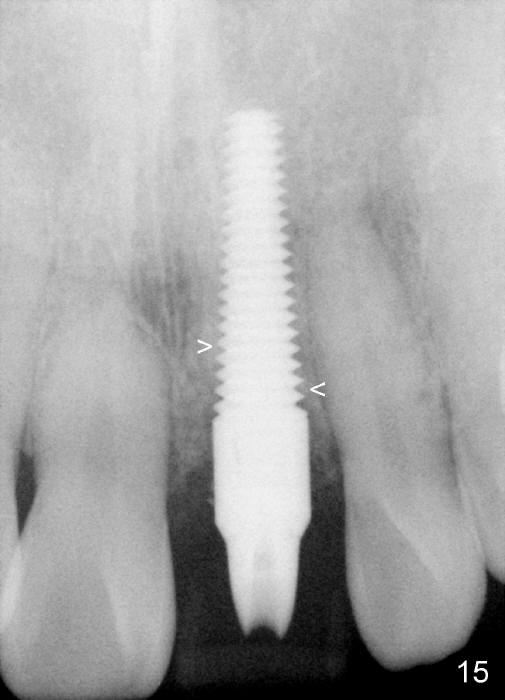

Bone expansion allows the implant (Fig.9 I) to have primary stability (insertion torque between 50 and 60 Ncm), since the cortex of the incisive canal is apparently intact. Allograft is placed in the labial gap (Fig.10, 11 *) following installation of the abutment (A). Finally an immediate provisional (Fig.10,12 P) is cemented. Fig.13,14 are taken 8 days postop. The patient returns 3 months postop (Fig.15,16). Osteointegration appears to have occurred (Fig.15 arrowheads) and is more obvious 9 months postop (Fig.17).